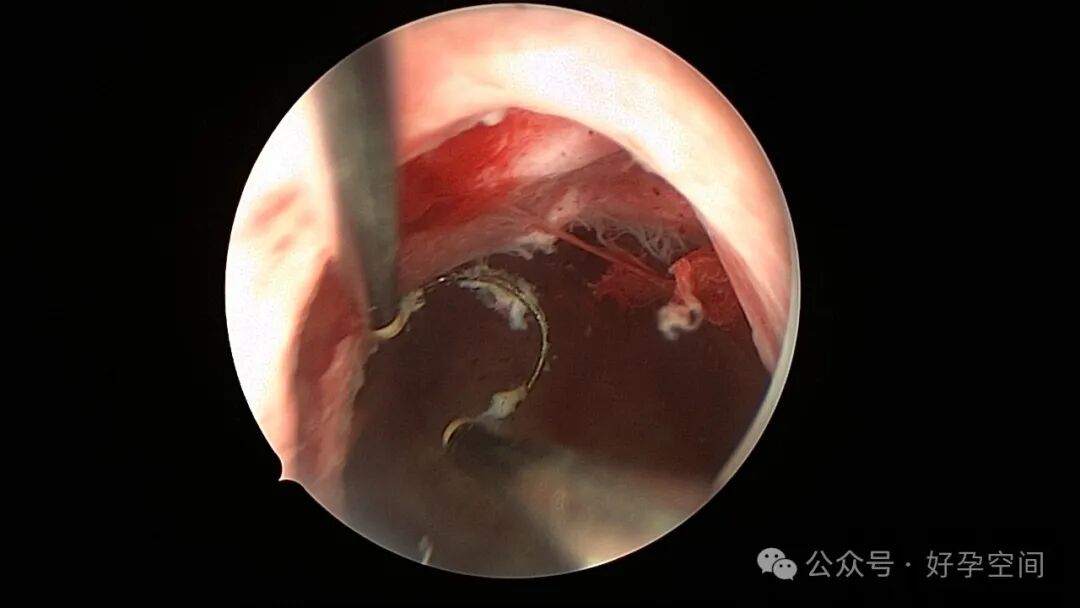

患者24岁,G6P3,顺产1次,双胎剖宫产1次。本次停经53天,计划外妊娠,行宫腔镜取胚及安环术。摘除胚胎后见宫腔右侧壁胚胎附着部位包块,约1.0cm*1.0cm*0.8cm,宫腔镜切除包块送病检,放置γ环一个,环两臂卷曲于右侧宫角,宫腔镜钩住环尾部下拉,上推节育环右臂,将环调整到正常位置。术后病检结果为“宫腔胎盘附着部位超常反应”。